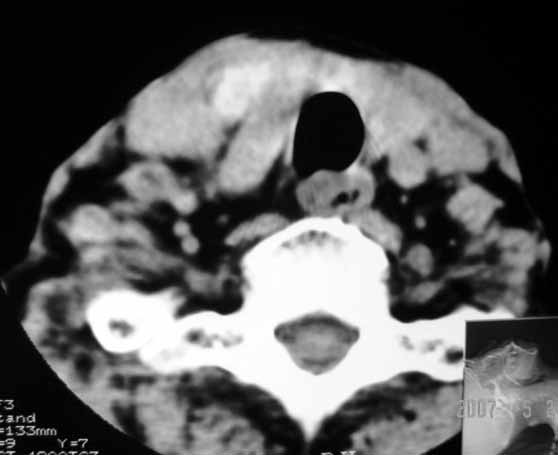

以下是引用jw-830在2007-5-24 15:33:00的发言:[br]右侧甲状腺增大,内可见低密度,病灶与周围软组织界线欠清晰,建议增强扫描除外甲状腺癌

以下是引用adams在2007-5-24 17:15:00的发言:[br]支持“ 右侧甲状腺增大,内可见低密度,病灶与周围软组织界线欠清晰,建议增强扫描除外甲状腺癌”。 [br] [br] [br][br] [br] [br]

以下是引用苯小孩在2007-5-24 15:26:00的发言:[br]左侧甲状腺腺癌或瘤,建议穿刺或核素进一步检查.